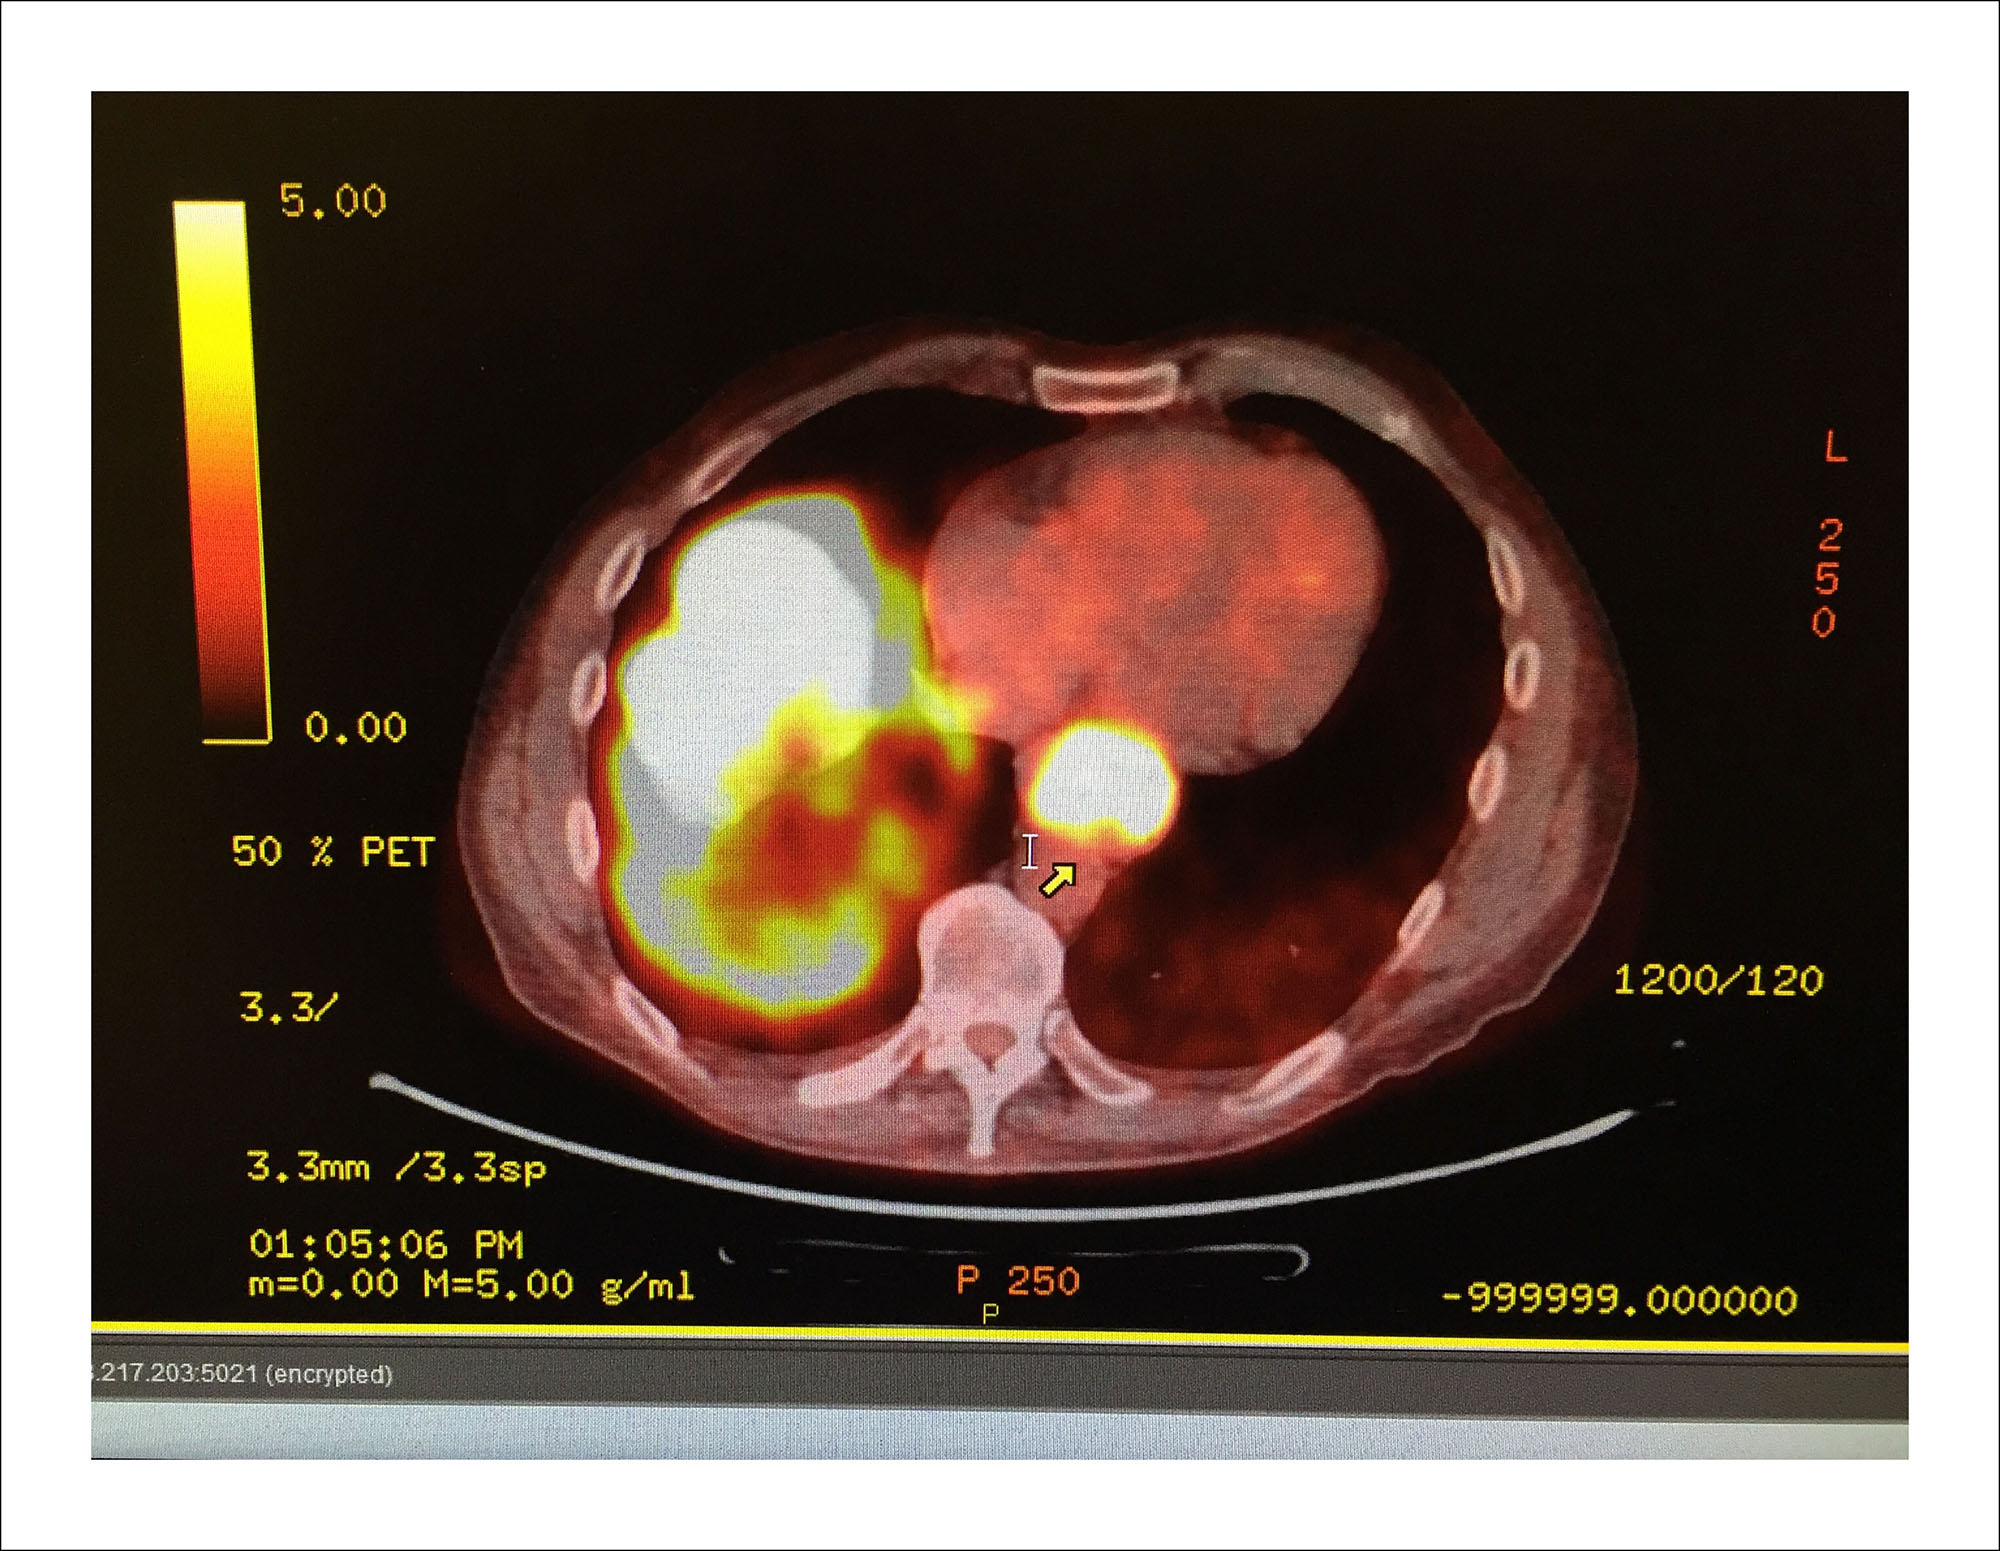

9/19/16 — Cancer cells grow faster and show more "heat" than normal. White hot is bad. The circle near the spinal cord is the tumor in my esophagus. The mass at left is in my liver.(Guy Reynolds/Staff Photographer)

9/19/16 — Cancer cells grow faster and show more "heat" than normal. White hot is bad. The circle near the spinal cord is the tumor in my esophagus. The mass at left is in my liver.

9/19/16 — This one had to be in color. PET scans show the heat profile of cells. Cancer cells grow faster and show more "heat" than normal. White hot is bad. The circle near the spinal cord is the tumor in my esophagus. The mass at left is my liver. The good news is the cancer isn't anywhere else. Chemo begins Thursday. Game on!(Guy Reynolds/Staff Photographer)

9/19/16 — This one had to be in color. PET scans show the heat profile of cells. Cancer cells grow faster and show more "heat" than normal. White hot is bad. The circle near the spinal cord is the tumor in my esophagus. The mass at left is my liver. The good news is the cancer isn't anywhere else. Chemo begins Thursday. Game on!